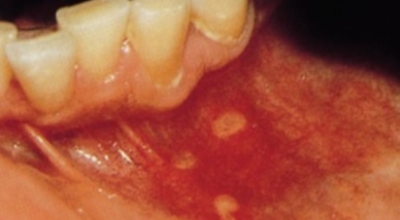

4. 구내염 원인 - 바이러스성 구내염

바이러스로 인해 나타나는 구내염도 있답니다. 단순 헤르페스 바이러스의 감염 원인인 '헤르페스성 구내염'은 주로 타액 과 같은 접촉으로 인해서 감염되어요. 또 곰팡이의 일종인 칸디다균은 원래 입안에 존재하는 상재균의 한 개지만, 만에 하나라도 면역력이 저하되면 증식해서 '칸디다성 구내염'을 병이 발생하게 됩니다.

바이러스성 구내염에 많이 관찰되는 다발성 구내염은 입 점막에 많은 소수포가 형성되어 찢어져 붕괴를 발생시킬 수이 있고 발열이나 강한 통증이 수반될 수 있습니다.